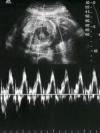

Третий скрининг осуществляется на 30-32 неделях беременности. Он проводится для того, чтобы оценить функциональное состояние малыша, и убедиться, что ребенок и плацента эффективно взаимодействуют. Эти исследования позволяют предупредить некоторые возможные проблемы.